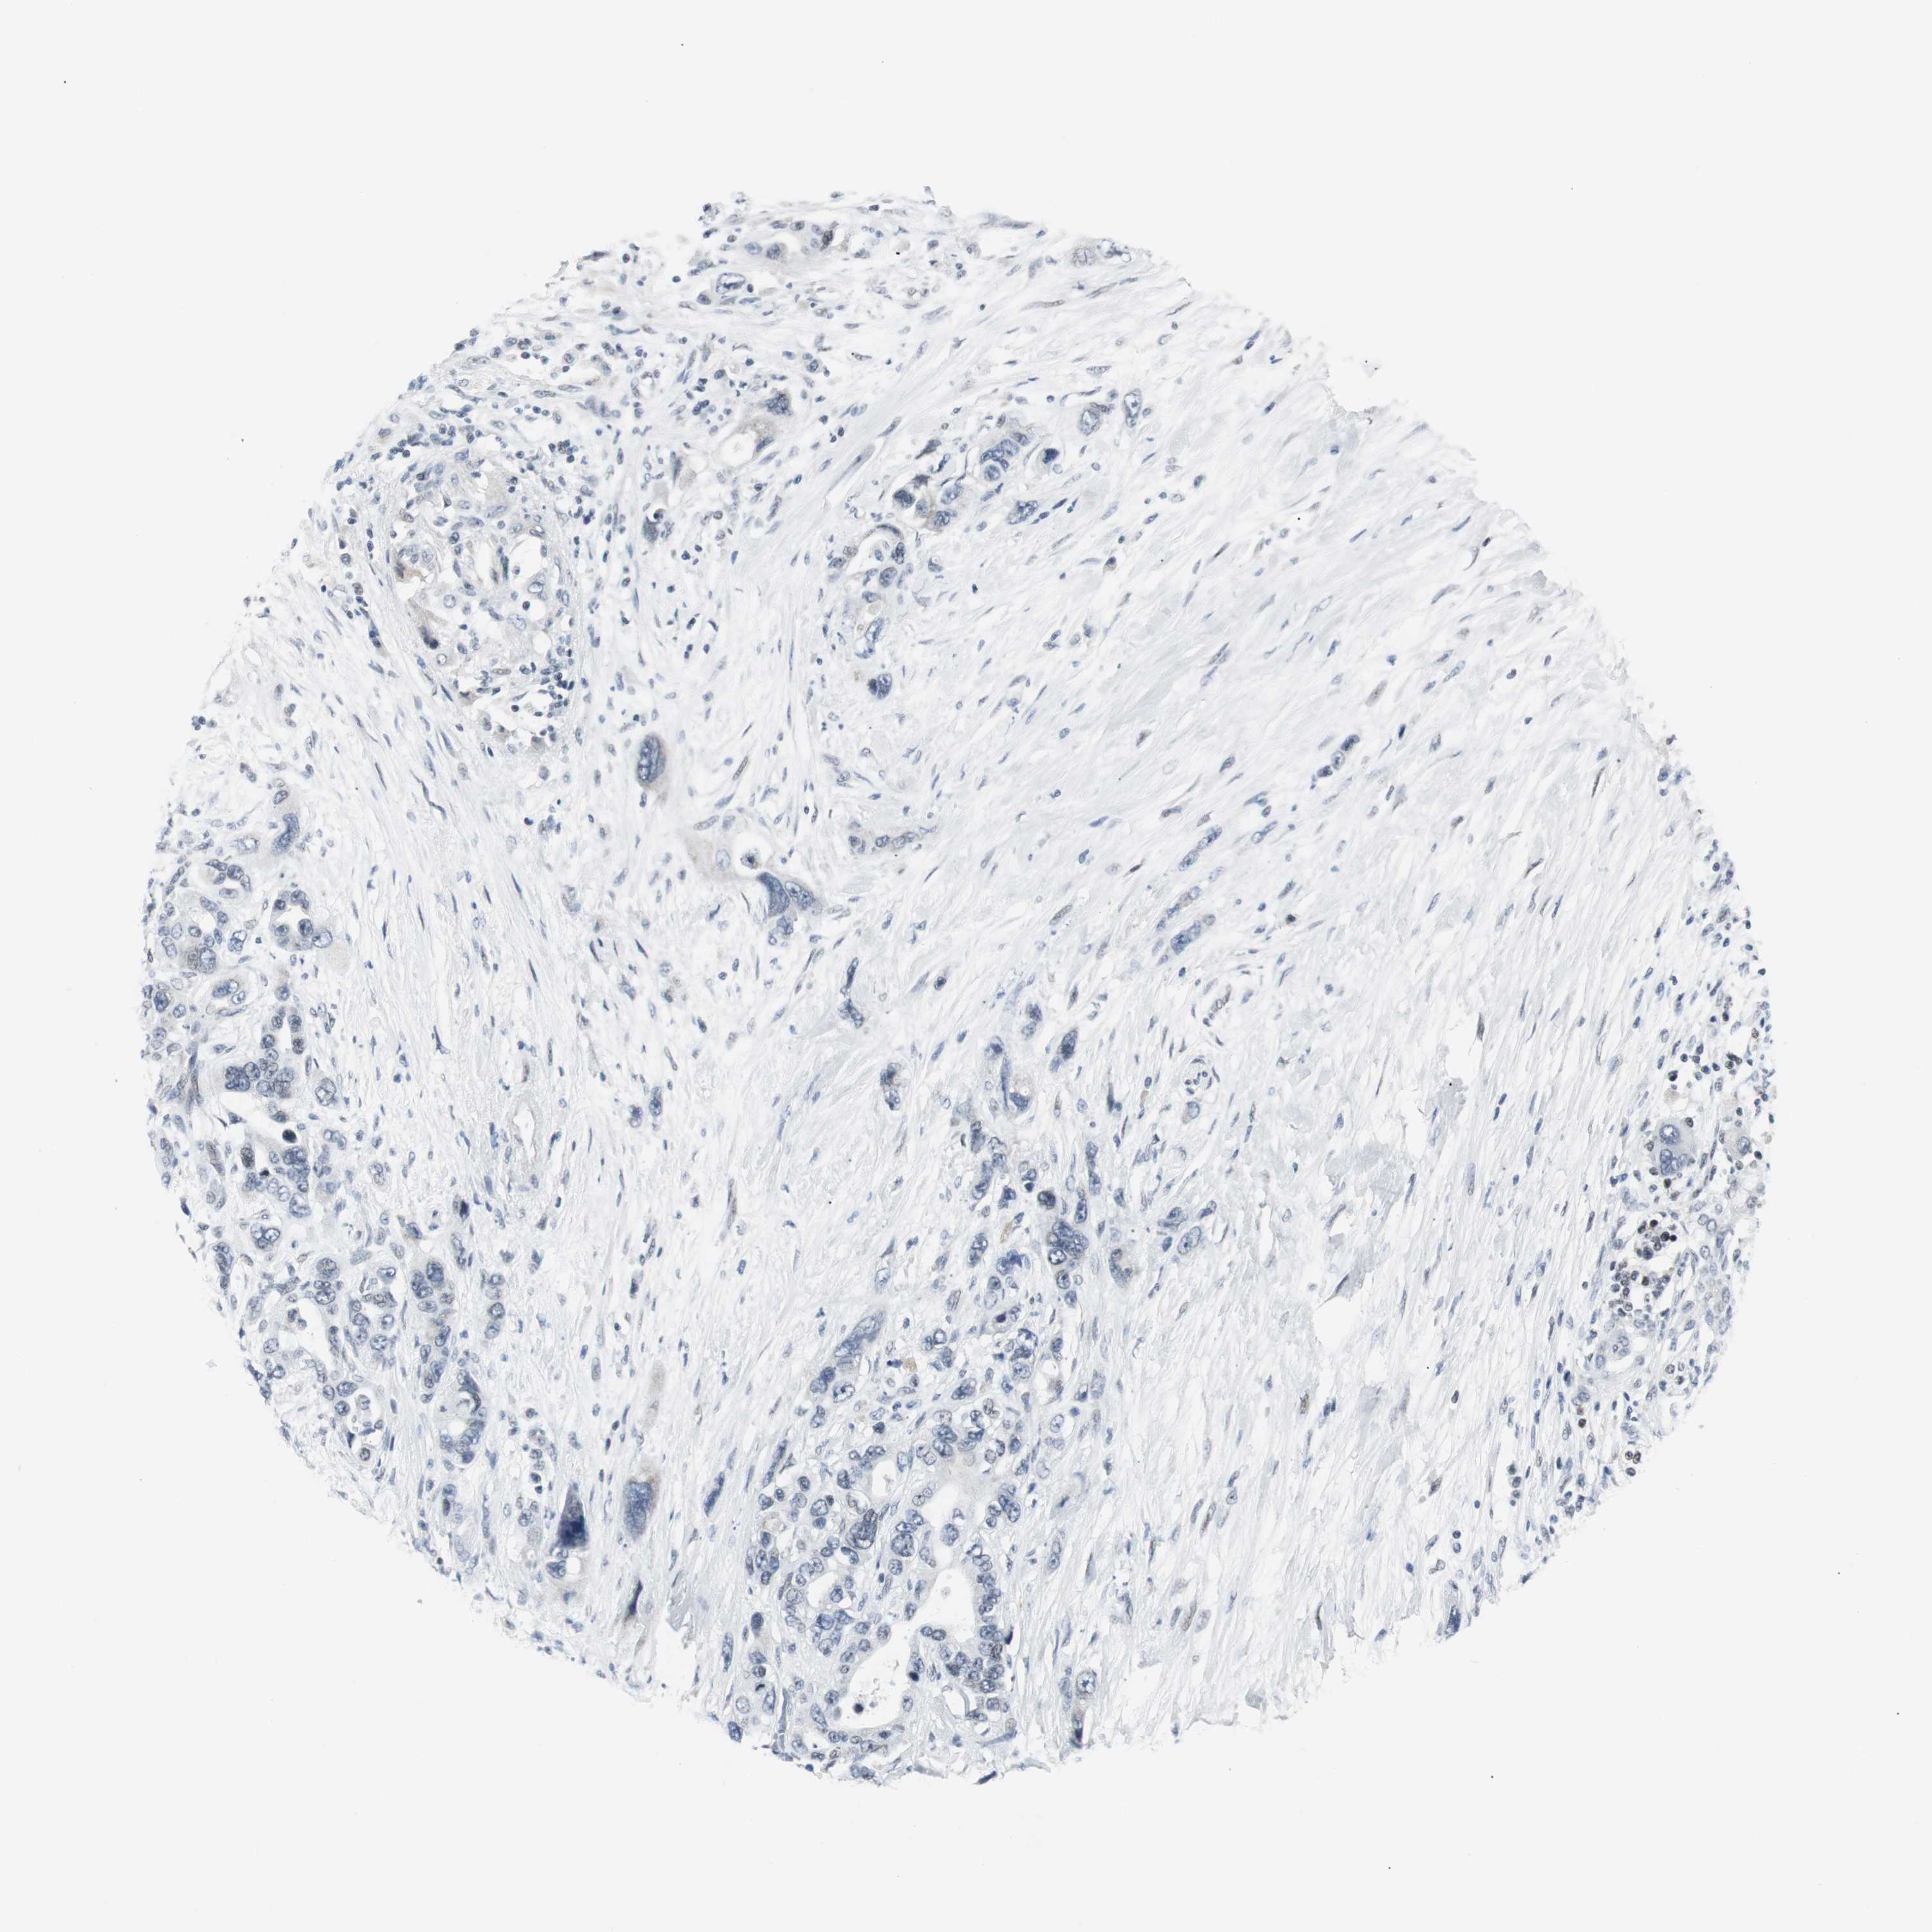

PANCREATIC CANCER - Protein expressioni

A mouse-over function shows sample information and annotation data. Click on an image to view it in a full screen mode. Samples can be filtered based on level of antibody staining by selecting one or several of the following categories: high, medium, low and not detected. The assay and annotation is described here.

Note that samples used for immunohistochemistry by the Human Protein Atlas do not correspond to samples in the TCGA dataset.

Antibody stainingi

Antibody staining in the annotated cell types in the current human tissue is reported as not detected, low, medium, or high, based on conventional immunohistochemistry profiling in selected tissues. This score is based on the combination of the staining intensity and fraction of stained cells.

Each image is clickable and will lead to virtual microscopy that enables deeper exploration of all samples and also displays staining intensity scores, fraction scores and subcellular localization as well as patient and tissue information for each sample.

Antibody HPA005544

Antibody CAB004508

Staining

High

Medium

Low

Not detected

Intensity

Strong

Moderate

Weak

Negative

Quantity

>75%

75%-25%

<25%

None

Location

Nuclear

Cytoplasmic/membranous

Cytoplasmic/membranous,nuclear

Adenocarcinoma, NOS

Adenocarcinoma, metastatic, NOS